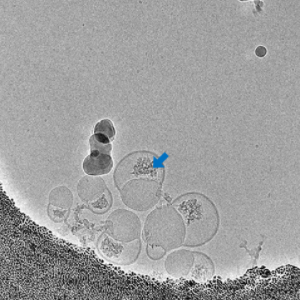

mRNA Localization by Thionine Staining

Amorphous mRNA is relatively loose and exhibits poor contrast in EM images, making it difficult to identify. Additional staining procedures are required for its localization. The staining mechanism of thioine is based on the interaction between its active functional groups and nucleic acids in the cell nucleus. The aromatic and heterocyclic structures within thioine molecule allow it to form π-π stacking interactions with the base pairs in DNA and RNA, thereby binding to the nucleic acid molecules. Additionally, the chlorine atoms and amine groups in thioine can interact with the negative charges present in the nucleic acid molecules, enhancing the binding affinity between the dye and the nucleic acids. At the EM level, the effect of thioine increases the density of mRNA, thereby enhancing its contrast in electron microscopy.

• Before Staining

• After Staining

Localization of mRNA in LNP Samples by Thionine Staining